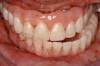

Fig 8. Failing dentition in an 82-year-old patient currently diagnosed with tardive dyskensia.

Figure 8

Fig 9. Transition line could not be hidden due to uncontrolled contortions of the facial musculature.

Figure 9

A patient with tardive dyskensia, for example, may experience dramatic changes in expressive facial activity and corresponding dysfunction in the muscle memory needed to repeat a centric position.19,20 Figure 8 and Figure 9 show an 82-year-old patient who had previously been treated for depression, had a failing dentition, and was diagnosed with tardive dyskensia. Extreme uncontrolled contortions of the facial musculature were evident in the patient when attempting to record a high smile line; removal of enough maxillary bone to hide the transition line was impossible. Dramatic compromises in occlusal scheme may be necessary to achieve even a moderately successful result; yet the implant approach realistically may be the only way to offer any functional improvement (Figure 10 and Figure 11).